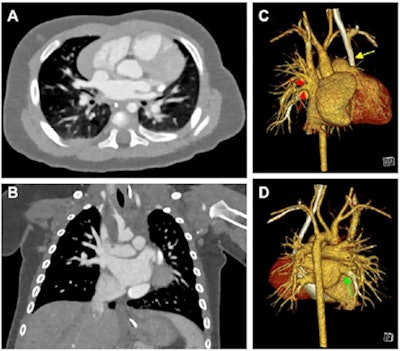

Cardiac photon-counting CT (PCCT) in a 174-day-old male infant with complex congenital heart defect. (A) Contrast-enhanced axial PCCT image shows sonographically suspected sinus venosus defect with partial anomalous pulmonary venous connection. Soft-tissue window is shown with a 0.6-mm section thickness. Intravenous contrast agent amount: 8 mL of iopromide. (B) Contrast-enhanced coronal PCCT image with soft-tissue window with 0.6-mm section thickness. (C) Anterior view of three-dimensional reconstruction shows a partial anomalous pulmonary venous connection of two separate lung veins from the right upper and middle lobe to the right superior vena cava (red arrows) and a persisting left superior vena cava (yellow arrow). (D) Three-dimensional reconstruction, posterior view. The diagnosis was confirmed at PCCT, and PCCT allowed for visualization of the partial anomalous pulmonary venous connection of two separate lung veins from the right upper and middle lobe to the right superior vena cava. One lung vein drains correctly to the left atrium (green arrow). A sinus venosus defect, an atrial septum defect, an enlarged right atrium, and a persisting left superior vena cava are shown. The only regular confluence of a single right lung vein into the left atrium is shown (D; green arrow). Image quality was rated as 5 of 5 (optimal). Dose-length product was 18. Approximated effective radiation dose, 0.58 mSv (conversion coefficient κ = 0.032 mSv/[mGy × cm]). Images and caption courtesy of the RSNA.Their study included CT exams of 113 infants who underwent contrast-enhanced PCCT (30), DSCT (83), or both types of exams (one) of the heart and thoracic aorta between January 2019 and October 2022. Median age of the children was 66 days.